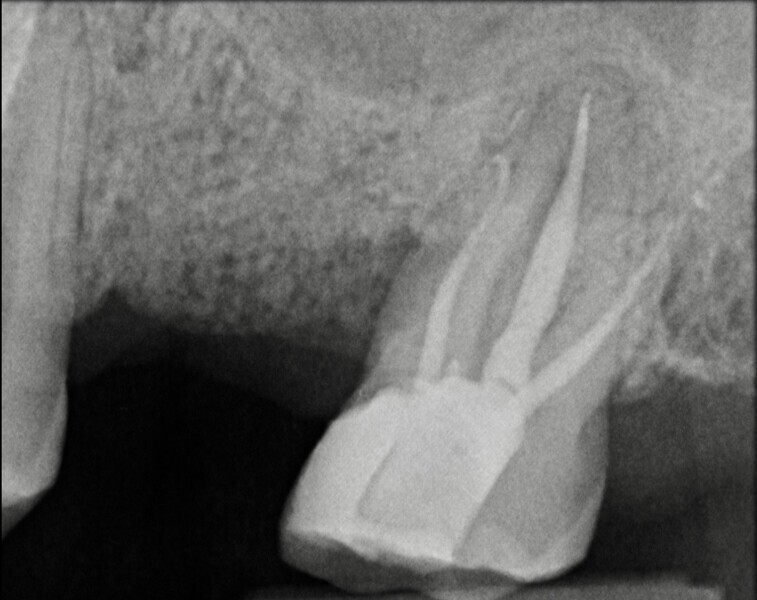

Use of 3D technology in the diagnosis and treatment of endodontic disease